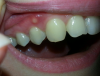

shush Опубликовано 1 марта, 2013 Автор Поделиться Опубликовано 1 марта, 2013 Здравствуйте!Спасибо всем за ответы.Вчера я попала к врачу, где была проведена консультация и сделаны снимки.Подтвердился свищевой ход.Начали выяснять от какого зуба.Под подозрение пала четверка(14) и шестерка(16), вскрыли мне этот волдырь и вставили туда гутаперчию(? извините, если неправильно говорю вашу терминологию).Меня озадачивает то, что болит 15 и 16 зуб(между ними где-то).Снимки прилагаю.На счет качества не уверена, пыталась как могла передать все детали.http://i072.radikal.ru/1303/78/c56ad614feff.jpghttp://s017.radikal.ru/i411/1303/f7/8ab216cf60c1.jpghttp://s003.radikal.ru/i203/1303/c7/943d66a8973f.jpghttp://i052.radikal.ru/1303/b4/0802cb967596.jpghttp://s47.radikal.ru/i118/1303/f1/3ad3959b5ab5.jpghttp://s019.radikal.ru/i643/1303/6b/458e5b3d39f3.jpg Ссылка на комментарий

Magdalena Опубликовано 1 марта, 2013 Поделиться Опубликовано 1 марта, 2013 Причина - зуб 14, хотя 16 надо тоже перелечивать. В 14 нужно исключить трещину корня. 1 Ссылка на комментарий